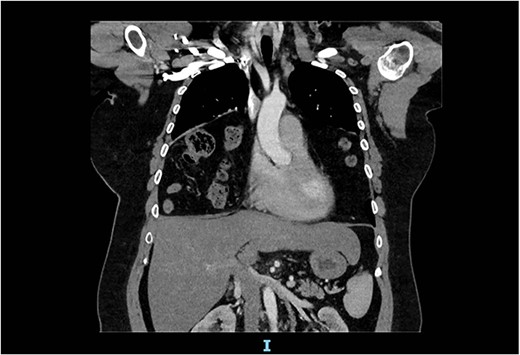

The spirometry results from her General Practitioner showed a restrictive pattern with FVC of 2.08L (55% predicted), FEV1 of 1.62L (54% predicted) and FEV1/FVC ratio of 0.78 (96% predicted). Her chest X-ray demonstrated a large hiatus or congenital hernia (Fig. 1). Subsequent computed tomography (CT) of the chest, abdomen and pelvis showed a large 88 × 48-mm defect of the anterior diaphragm consistent with MH. Hernial contents extended to the superior mediastinum and were primarily large bowel and omentum, with no intestinal obstruction (Figs 2–4).

Arterial contrast CT of the chest. Axial slice at the T4/5 level showing herniation of large bowel, small bowel and omentum into the chest cavity. The defect in the anterior diaphragm measures 88.2 mm × 48.2 mm. Of note is the significant reduction in the size of the lung fields.